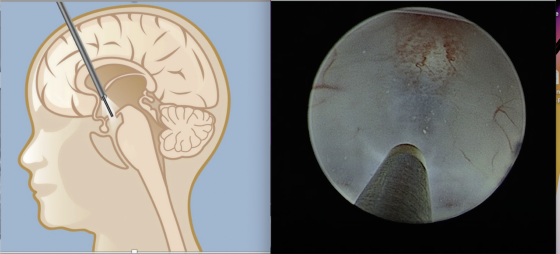

微创脑室造口术(Endoscopic third ventriculostomy-ETV)。

我告诉她说,脑积水的治疗方式主要有两种,第一种是脑室腹腔引流术(VP shunt),第二种是微创脑室造口术(Endoscopic third ventriculostomy),龙妈妈考虑了一下,选择了第二种治疗方式。

手术时,我借助内视镜深入龙妈妈的颅底脑室开一个小洞,让脑脊髓液可以从这个开口流出,恢复正常循环。手术耗时45分钟左右,术后清醒过来时,龙妈妈的眩晕和不适症状已经大有改善,住院3天后,我就批准她回家了。